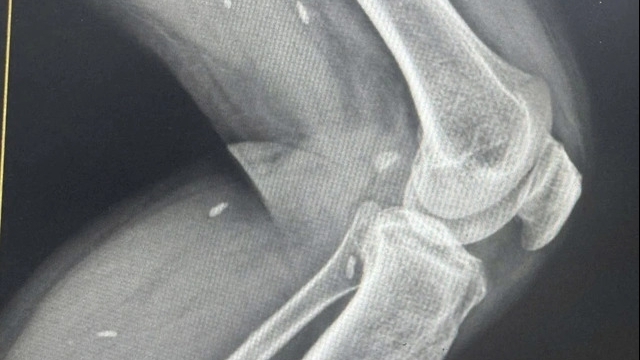

Bác sĩ cho biết khi tiếp cận, bệnh nhi đã ngưng tim, ngưng thở, đồng tử giãn và mất phản xạ. Dù các bác sĩ nỗ lực hồi sinh tim phổi suốt 70 phút, đặt nội khí quản nhưng bé vẫn không qua khỏi.

| Thức ăn nghẹt dính vào ống nội khí quản sau khi hồi sinh tim phổi thất bại (Ảnh: BVCC) |